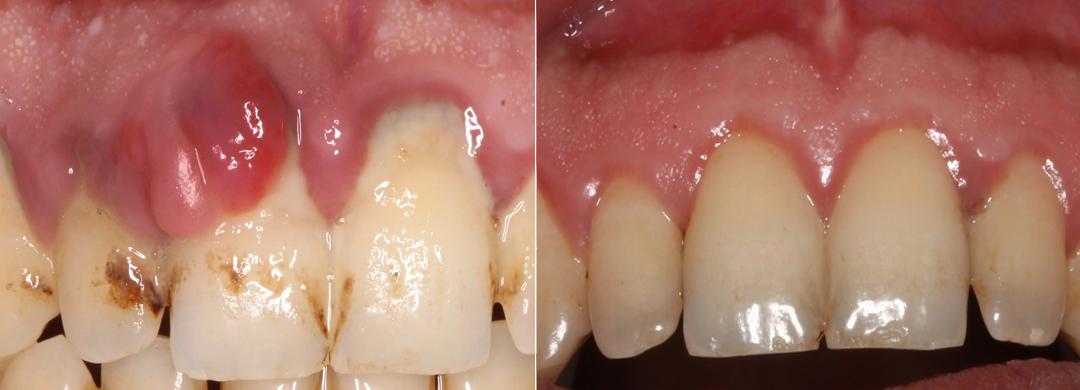

Step 3 — Supports Gum Repair Within 7 Days

Thanks to an innovative gum-repair technique developed by researchers at Heidelberg University, YUNPSO® BeeTakt Oral Repair Solution is formulated with Tideglusib—an active ingredient known for activating gum stem cells and supporting natural tissue regeneration.

Tideglusib helps repair damaged gum tissue and noticeably improves gum health within just 7 days. By strengthening gum structure and restoring vitality, this treatment promotes healthier, more resilient gums in a remarkably short time.